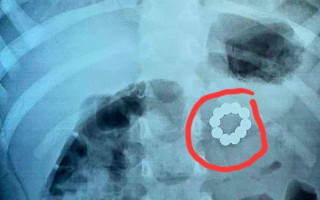

У Франківську хірурги прооперували трирічну дитину, яка ковтнула 21 магніт

21:46, 13 жовтня 2024

Лікарі витягнули 21 магніт з шлунково-кишкового тракту 3-річної дівчинки.